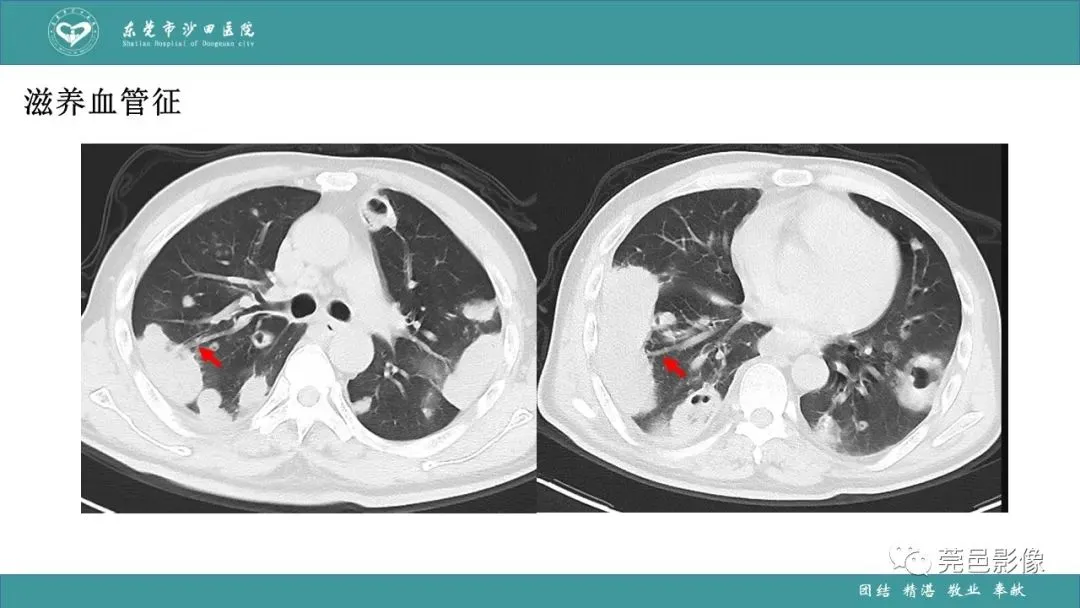

>课件 | 肺炎克雷伯杆菌肺炎影像学诊断与鉴别诊断

课件 | 肺炎克雷伯杆菌肺炎影像学诊断与鉴别诊断